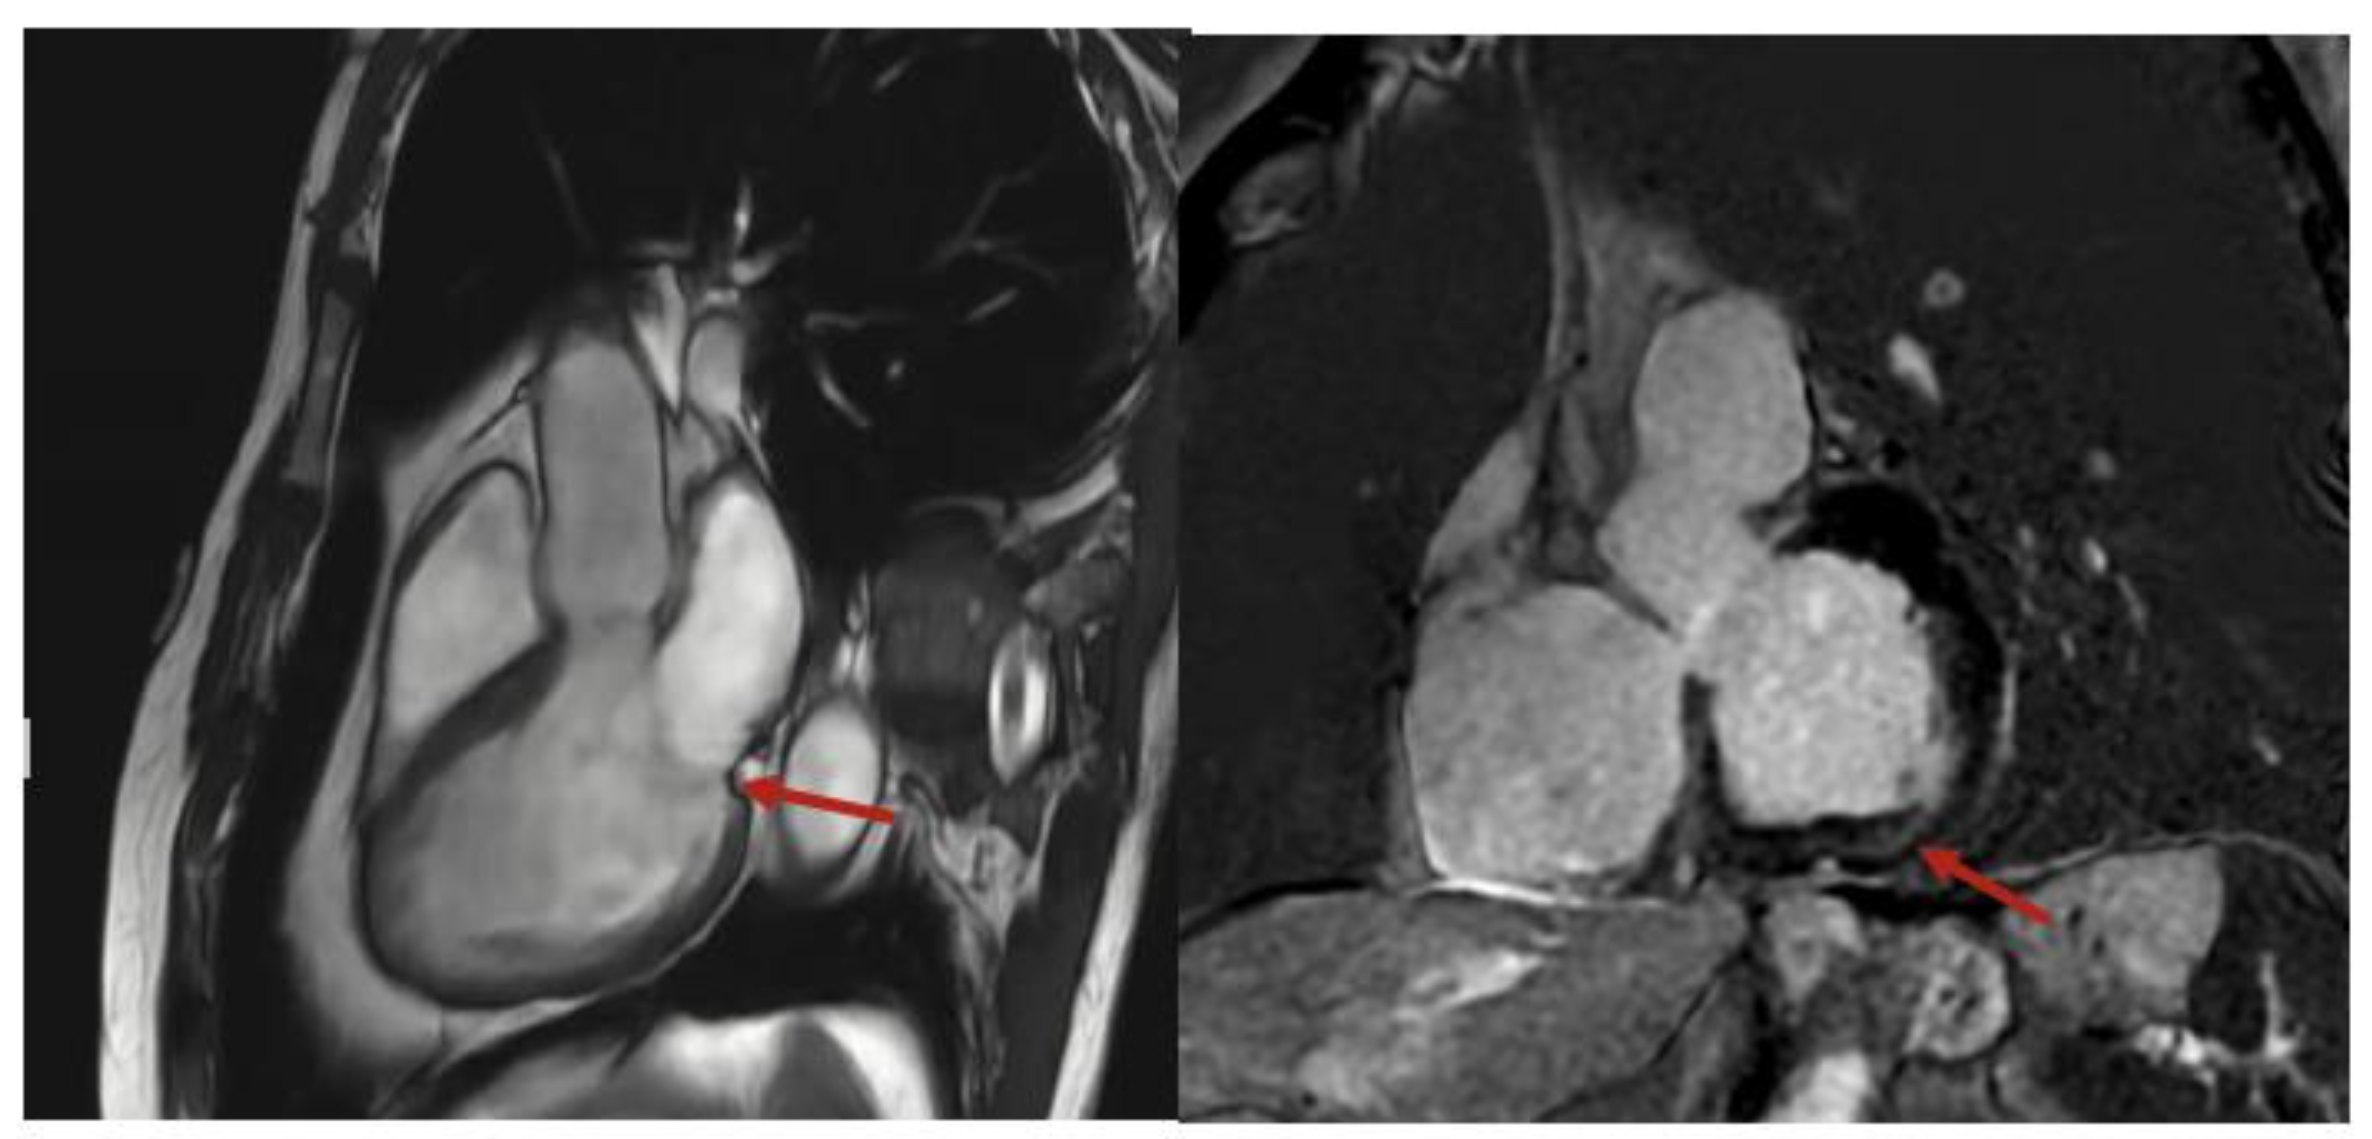

2. Case Presentation